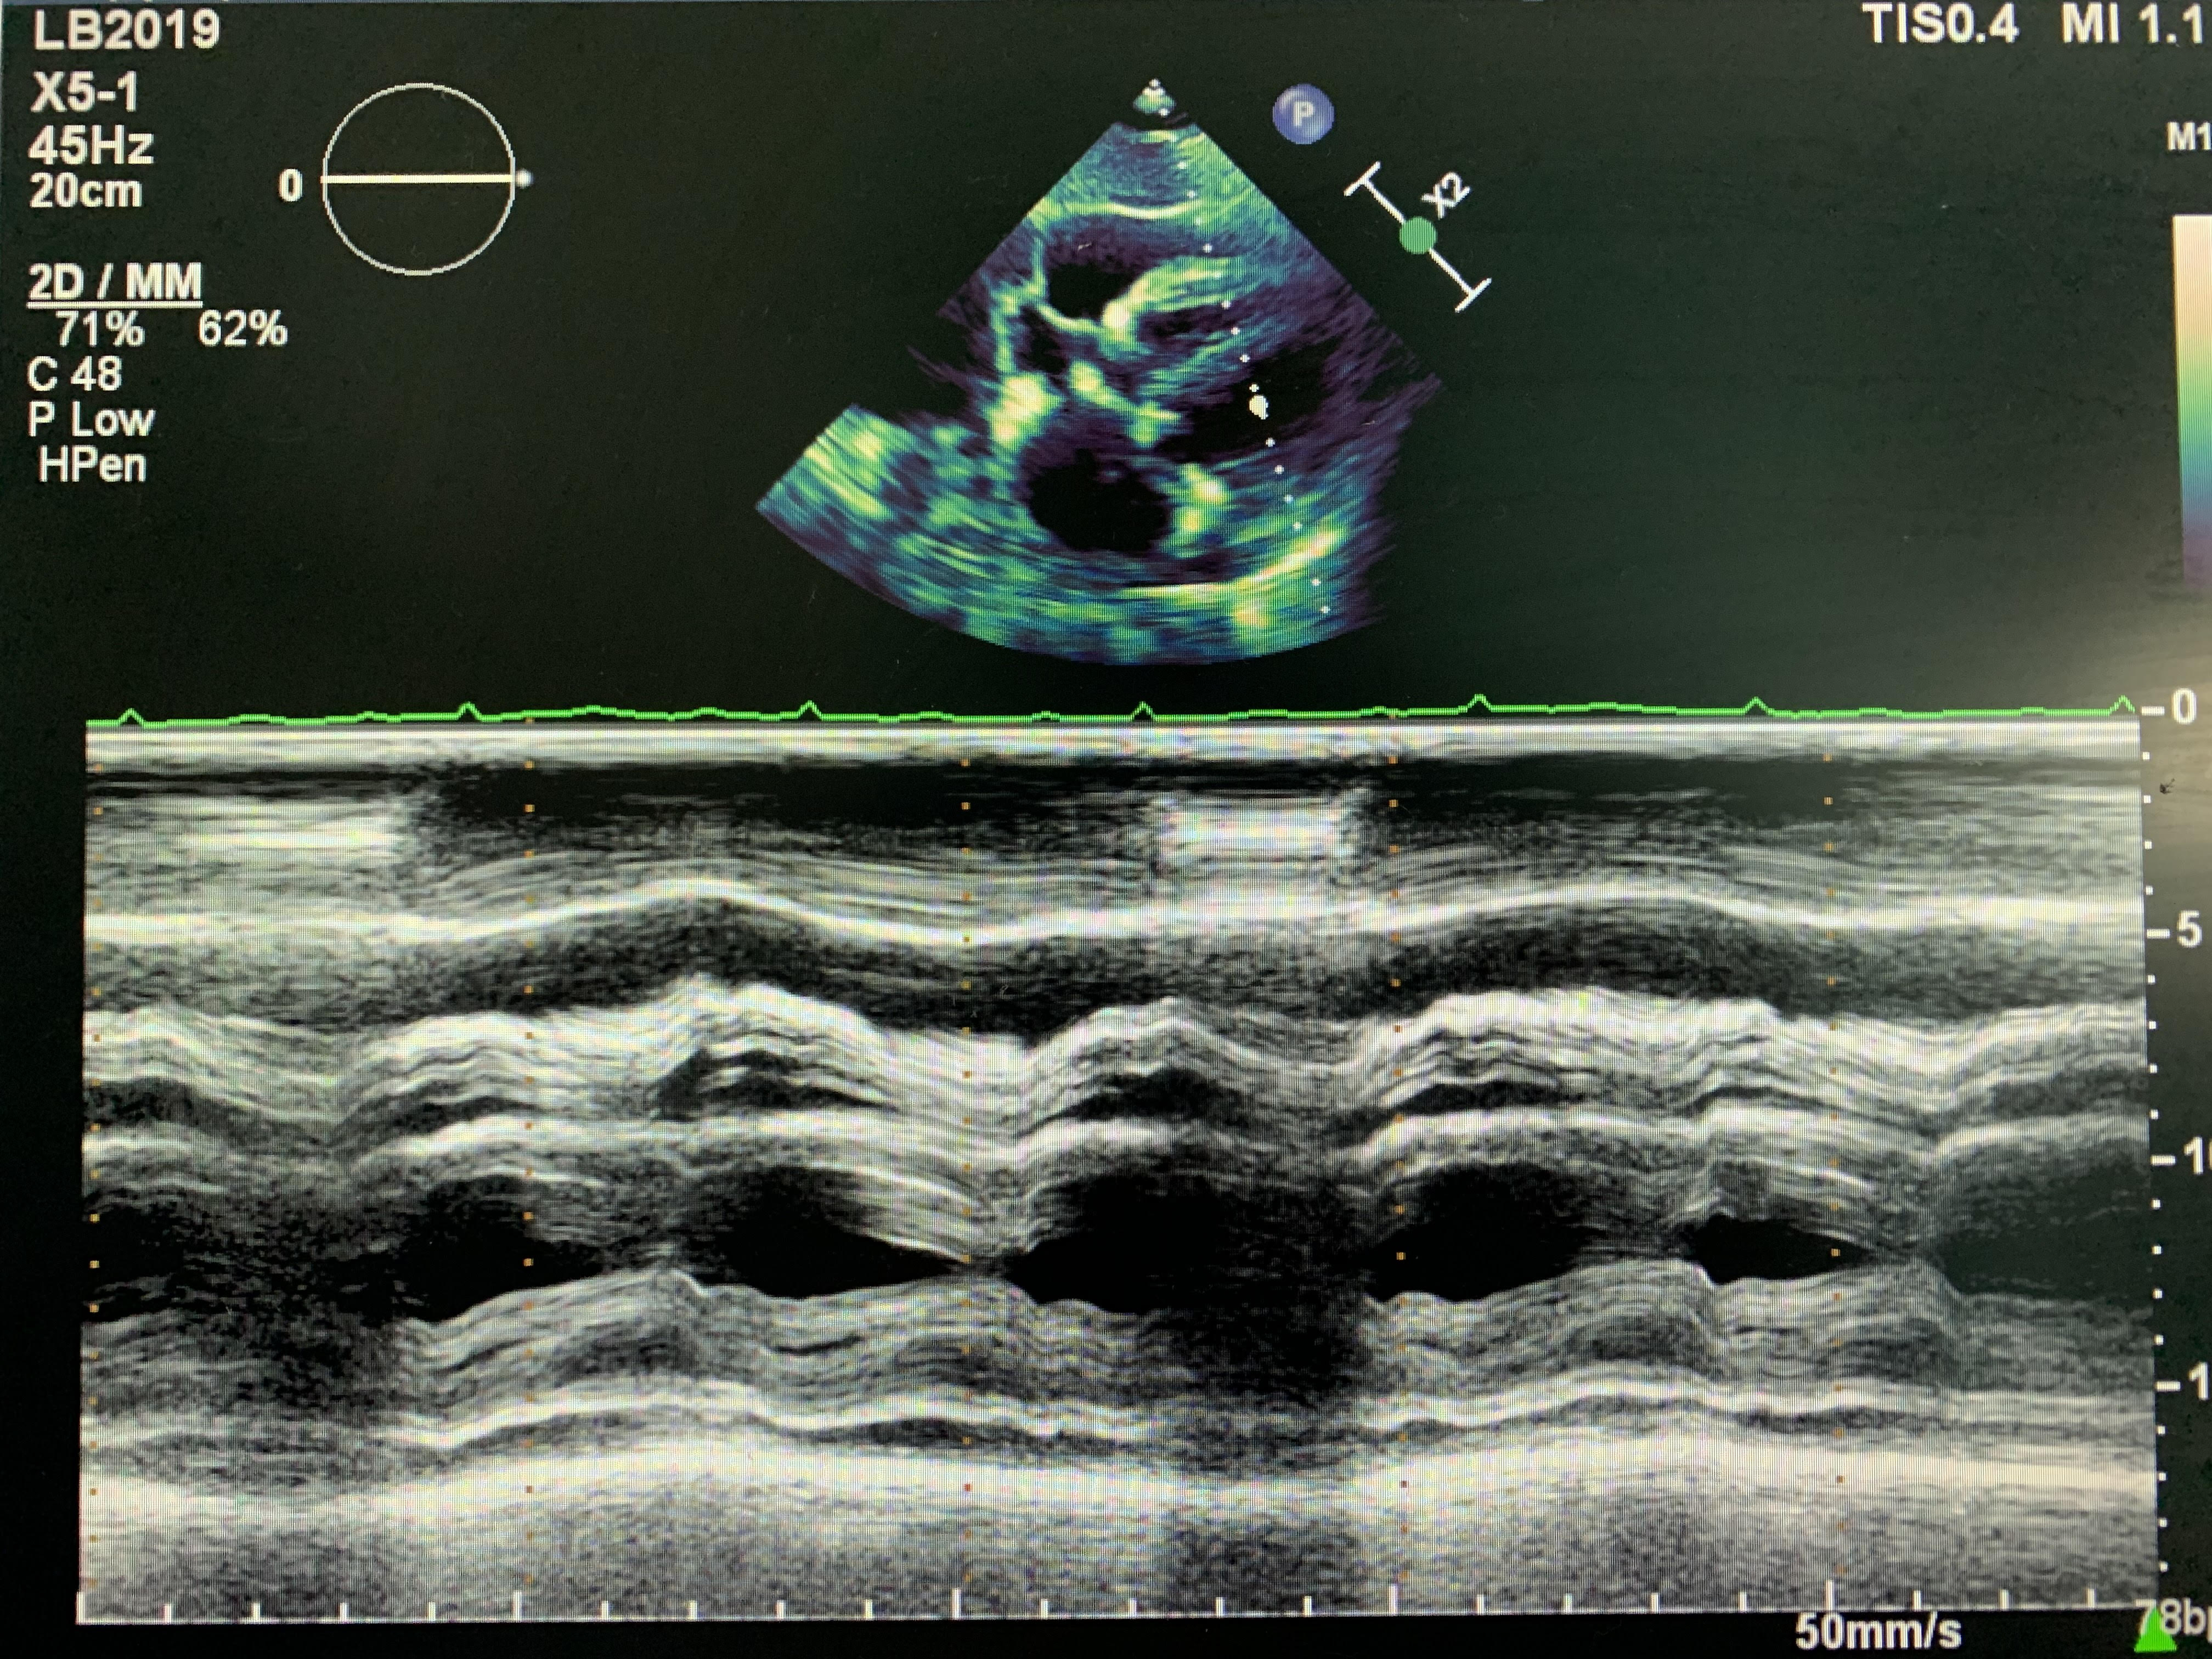

A 78 y/o Female presents for complete echocardiogram with a history of dyspnea on exertion. Patient is on 4 L of oxygen, unable to breathe laying supine. Breathing gets better as she sits up. Below are just a few images of her echo.

It was agreed by the physicians that the patient had a large pericardial effusion and her right atrium was collapsing. Further treatment to be determined.

Below pictures are taken from the SUB4 view only, as the patient’s respiratory variation didn’t show any changes.